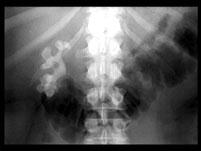

问题 女,39岁,腹痛,腹部平片+IVP如图所示,下列说法正确的是 ( )

选项 A、右肾集合系统内高密度影考虑为右肾结石 B、右肾集合系统内高密度影考虑为右肾结核钙化 C、右输尿管未见造影剂 D、左肾可见重复的肾收集系统 E、右肾集合系统内可见大的鹿角状高密度影

答案 ACDE